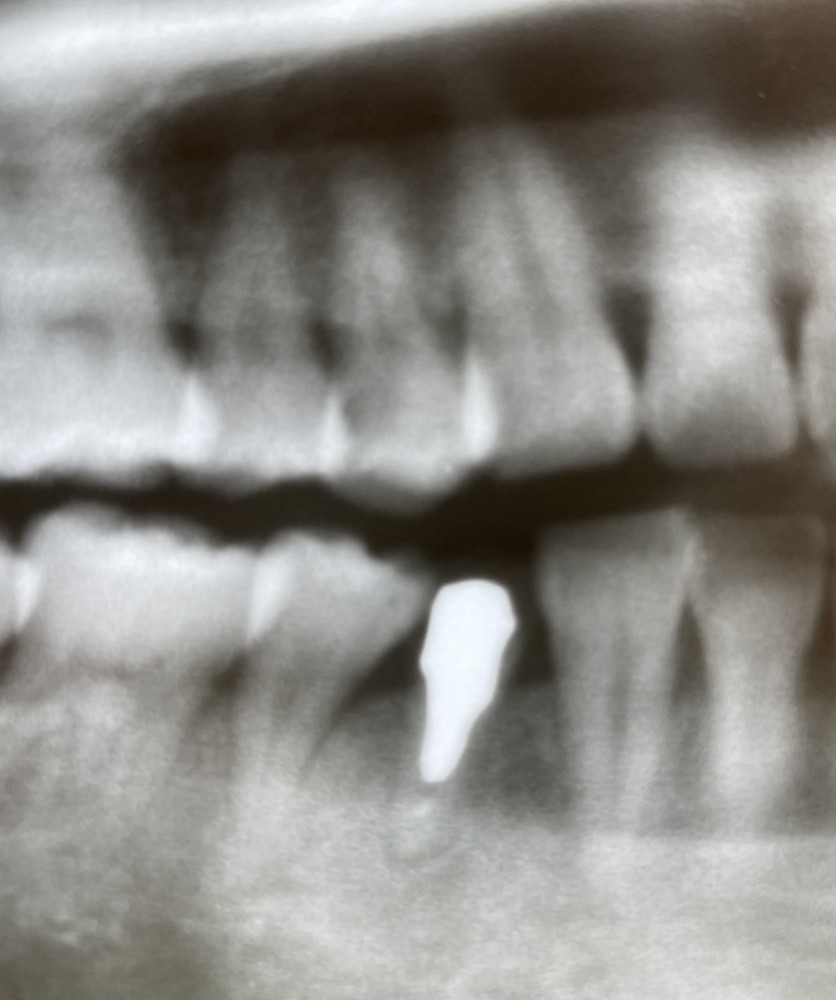

下は、術後6年経過後のエックス線写真です。

↓↓↓↓↓↓↓↓↓↓↓

右下4は経過良好ですが、

右上4に遠心c認められます。

直覆してメタルインレー修復行いました。

咬合面遠心窩洞にできたため、

審美的にはご本人さまは満足されています。